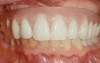

Fig 12. Treatment to restore this patient’s smile and functionability commenced when she was 102 years old.

Figure 12

Fig 13. An All-on-4 approach was used to treat both arches with interim immediate and eventual definitive restorations.

Figure 13

Fig 14. Final restorations used for 6-1/2 additional years.

Figure 14

This is an unfortunate mindset in that current advances in protocol and technology can result in significant advantages in addressing some or most of these concerns. The patient shown in Figure 12 may serve to illustrate this point. She had a destroyed maxillary dentition, a less-compromised but highly unesthetic mandibular component, and a single goal: to be able to "smile at my grandchildren again." In consultation with her and her family, it was decided that a double-arch fixed implant approach would most realistically address her esthetic goals and provide her with the desired prosthetic result. She was 102 years old at the time of initial consultation. Using a staged operating-room approach, provisional restorations were initially delivered, followed by subsequent definitive hybrid final restorations. She was able to use these comfortably for the next 6-½ years (Figure 13 and Figure 14).